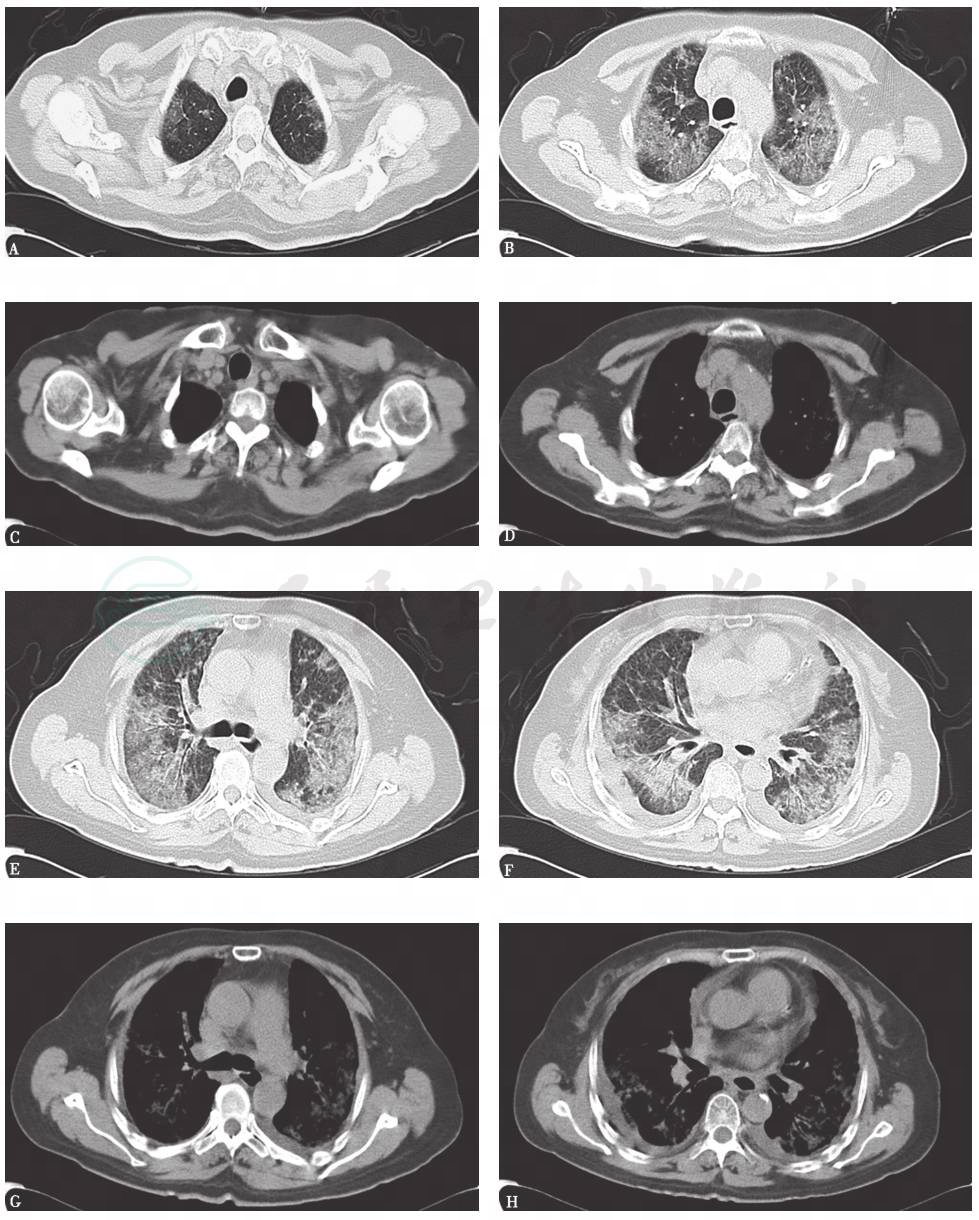

胸部CT:双肺弥漫间质性病变伴多发小结节(图1)。2个月后,随着病程延长,原有结节样病灶增多,病灶融合,形成磨玻璃及实变影,并出现双侧胸腔积液和少量心包积液(图2)。

图1 胸部CT表现(2014-03-05)

图2 胸部CT表现(2014-05-22)

4.胸部影像学表现由双肺弥漫性磨玻璃影并多发小结节样改变,逐渐进展至大片磨玻璃影、局部实变结节并双侧胸腔积液。

5.应用激素后,患者临床症状有所好转,但影像学表现持续进展。